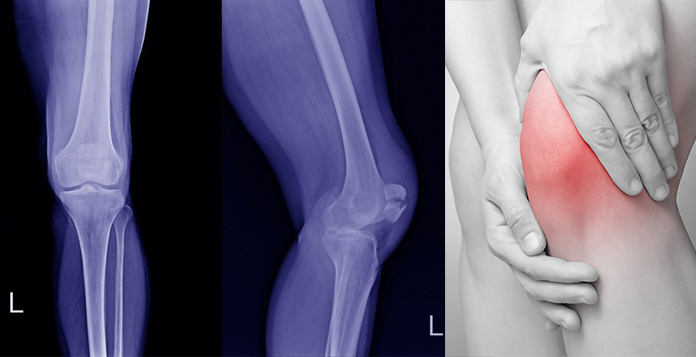

KNEE FRACTURES

Knee joint is between lower end thigh (femur) bone, upper end of Shin bone (Tibia) and Knee cap (patella). Fracture can invole either lower end of femur, Upper end of tibia or Patella. Fractures around knee joint are more often associated with ligament injuries (ACL, PCL, MCL, LCL) & Meniscal (Medial or Lateral) Tears.

Symptoms

- Pain

- Swelling

- Inability to move the joint

- Inabiliy to bear weight

- Joint deformity

Investigations

- X-rays